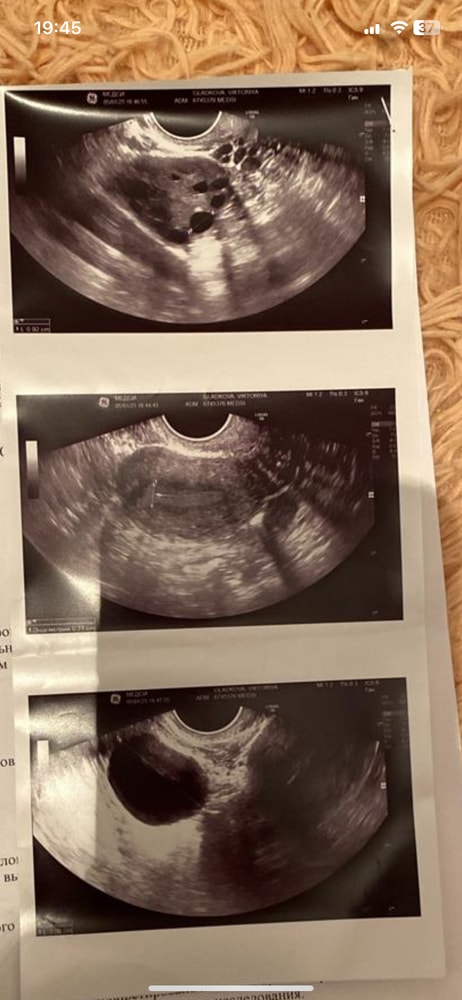

Гинекологические заболеванияПодскажите у кого получилось забеременеть с поликистозом яичников без лапароскопии . Буду признательна за ваши ответы и истории . Делали еще эхогсг нашли синтехию но при гистероскопии ее не было .

Анастасия, стимуляцию не решаются делать ,бояться что будет гиперстимуляция. У меня овуляции нет к сожалению. За год все ановуляции. Ни одна не стрельнула. И чтобы эти дни пошли принимала ипрожин . По другому никак